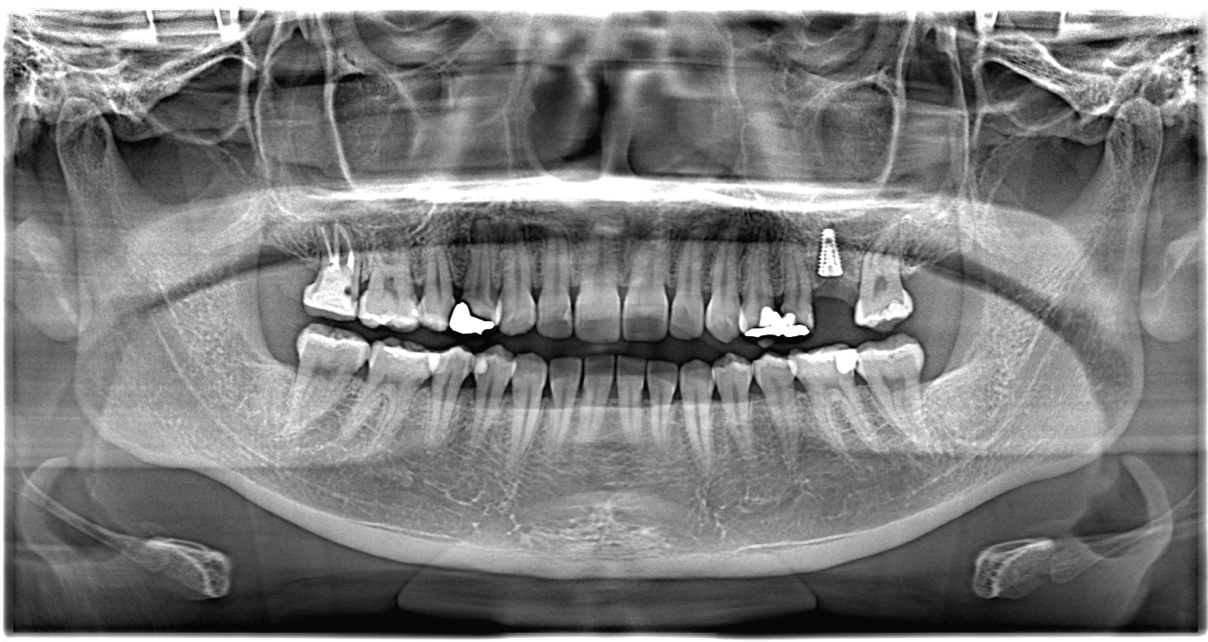

当院では初診時より、口腔内写真を撮影し その後CT(3次元上で骨の幅や高さがわかるレントゲン)でインプラントが可能かどうかを診断。

しっかり診断したのち処置していきます。

左上を抜歯後インプラント希望のため、CT撮影

骨の高さが少し足りないためクレスタルアプローチを実施しました。